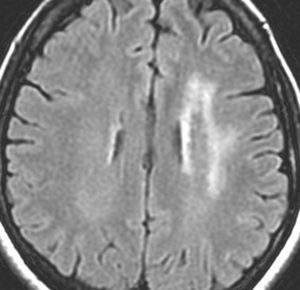

左前頭葉のグリオーマ oligodendroglioma に54グレイ27分割の放射線治療が行われました。治療直後のフレア画像(左)では深部白質に異常信号はありません。

2年後のフレア画像です

側脳室壁と深部白質 (半卵円中心) にびまん性の高信号が出現しています

無症状です

グリオーマが再発したのではないかと思ってしまいますが違います